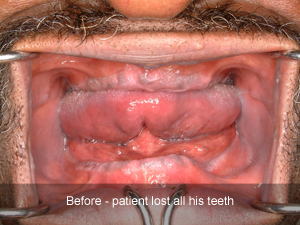

Clinical Cases